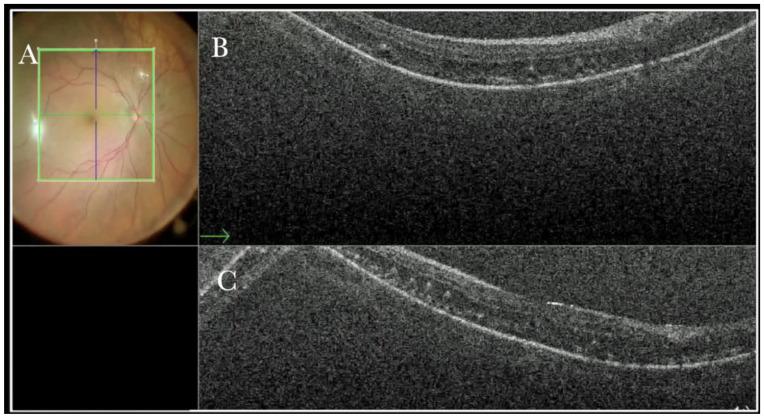

术中光学相干断层扫描在实际玻璃体视网膜手术中的作用

The Role of the Intraoperative Optical Coherence Tomography for Vitreoretinal Surgery in a Real-Life Setting.

To descriptively report the advantages and the feasibility of microscope-integrated intraoperative optical coherence tomography (i-OCT) in managing different vitreoretinal diseases in a real-life setting.

METHODS

We conducted an observational retrospective study involving 265 eyes that underwent elective retinal surgery and intraoperative OCT between 1 September 2018 and 1 October 2022 at Eyecare Clinic (Brescia, Italy).

RESULTS

52 epiretinal membranes, 30 retinal detachments, 60 high myopic eyes, 30 choroidal transplants, 40 macular holes, and 32 vitreo-proliferative retinopathies underwent vitreoretinal surgery and intraoperative OCT scans. The i-OCT was a useful diagnostic exam for all cases and significantly influenced our surgical management.

CONCLUSIONS

i-OCT is a helpful surgical tool in ophthalmic surgery as it provides real-time feedback of tissue anatomy to surgeons, thereby guiding decision-making. Moreover, it provides additional information on the microarchitectural changes after instrument-tissue interactions, further guiding procedures when necessary and possibly reducing unessential surgical maneuvers.